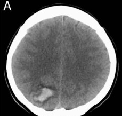

脑动静脉畸形(AVM)在破裂出血前往往没有症状。一些患者确实出现了没有破裂的症状这往往发生在中年,男性比女性略多。症状的严重程度可能差异很大;在一些人身上,身体变得衰...

脑动脉瘤一旦破裂,凶险,且随时有再次出血的风险。到底什么人容易得脑动脉瘤?脑动脉瘤是怎么形成的?一文详细解答...